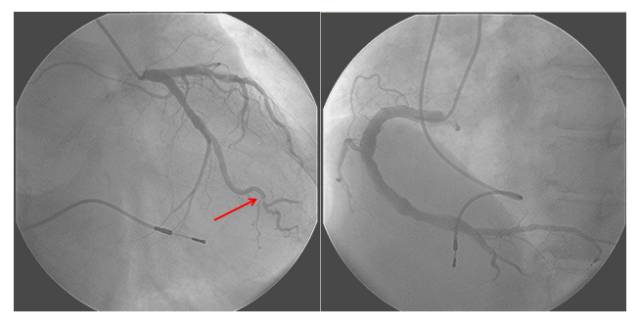

冠状动脉造影提示:左前降支斑块浸润,回旋支远端50%狭窄,右冠瘤样扩张。